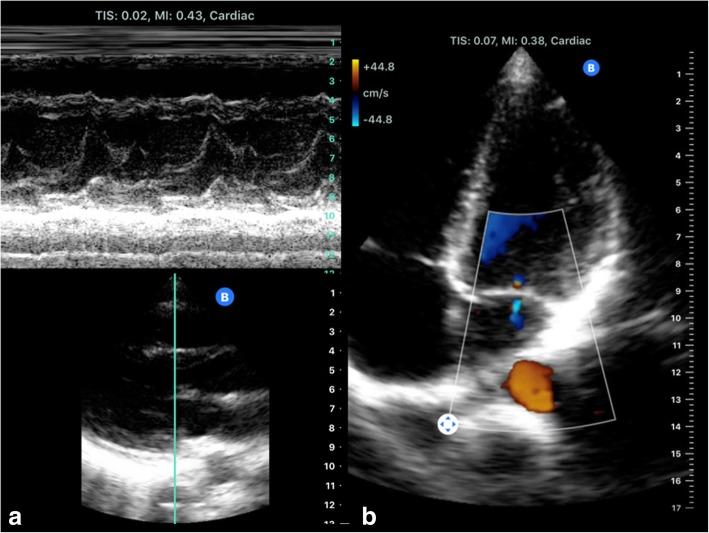

The use of portable ultrasound (US) devices has increased in recent years and the market has been flourishing. Portable US devices can be subdivided into three groups: laptop-associated devices, hand-carried US, and handheld US devices. Almost all companies we investigated offer at least one portable US device. Portable US can also be associated with the use of different US techniques such as colour Doppler US and pulse wave (PW)-Doppler. Laptop systems will also be available with contrast-enhanced US and high-end cardiac functionality.Portable US devices are effective in the hands of experienced examiners. Imaging quality is predictably inferior to so-called high-end devices.The present paper is focused on portable US devices and clinical applications describing their possible use in different organs and clinical settings, keeping in mind that patient safety must never be compromised. Hence, portable devices must undergo the same decontamination assessment and protocols as the standard equipment, especially smartphones and tablets.

近年来,便携式超声(US)设备的使用有所增加,市场蓬勃发展。便携式超声设备可细分为三类:与笔记本电脑相关的设备、手提式超声设备和手持式超声设备。我们调查的几乎所有公司都至少提供一种便携式超声设备。便携式超声还可与不同的超声技术结合使用,如彩色多普勒超声和脉冲波(PW)多普勒。笔记本电脑系统还将具备超声造影增强功能和高端心脏功能。便携式超声设备在经验丰富的检查人员手中是有效的。成像质量预计低于所谓的高端设备。本文重点关注便携式超声设备及其临床应用,描述它们在不同器官和临床环境中的可能用途,同时牢记绝不能损害患者安全。因此,便携式设备必须与标准设备,尤其是智能手机和平板电脑,接受相同的去污评估和规程。